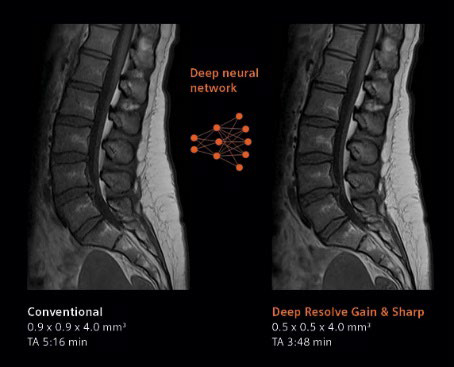

デジタル化により高画質と撮像時間の短縮を実現するべく,画像再構成にAI技術を用いて開発されたのがDeep Resolve(ディープ・レゾルブ)。

Deep Resolveは,ディープラーニング(深層学習)とターゲットデノイジング(ノイズの標的除去)により画像のノイズ除去や撮像した画像を高分解能化することで,高品質な画像の取得と撮影時間の短縮※を可能にする。検査精度やワークフローの向上のほか,被検者の快適性や質の高い医療へのアクセス向上が期待される。

左:ルーチン検査画像,右:Deep Resolveによる再構成画像